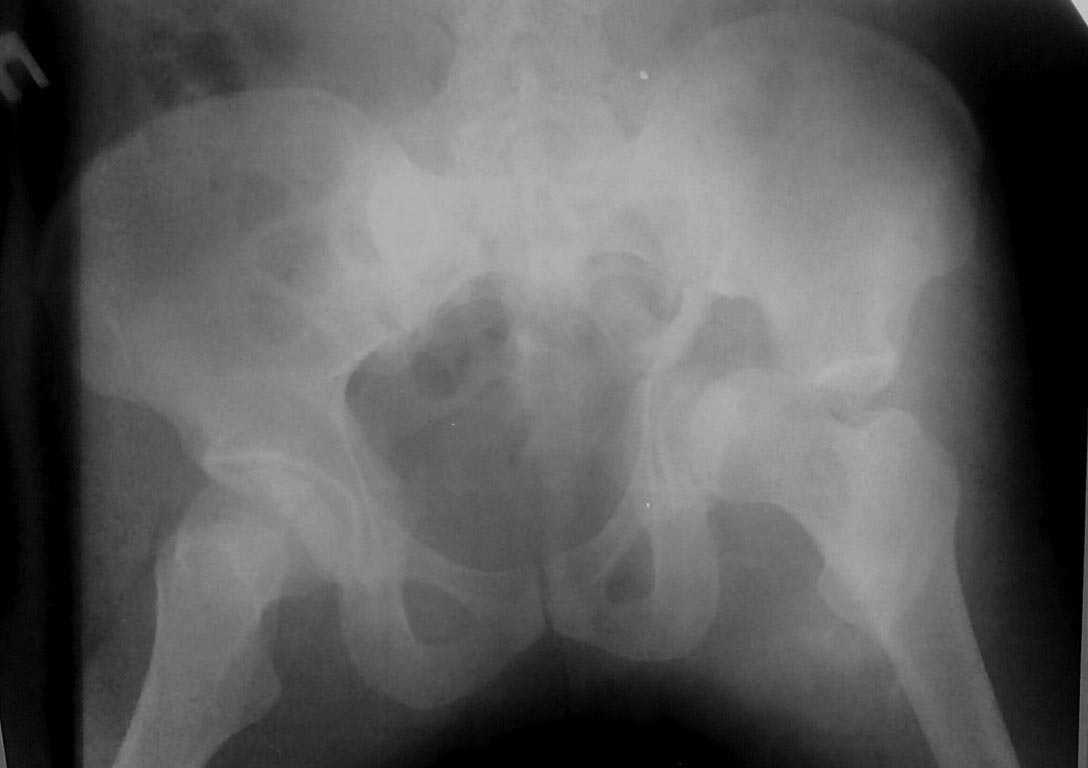

[Ortho] Перелом таза

Добрый день.Мужчина 30 лет. ДТП 20/9/17Перелом таза слева, на снимке все

видно. КТ сделана, но сейчас не располагаю.Требуется остеосинтез.